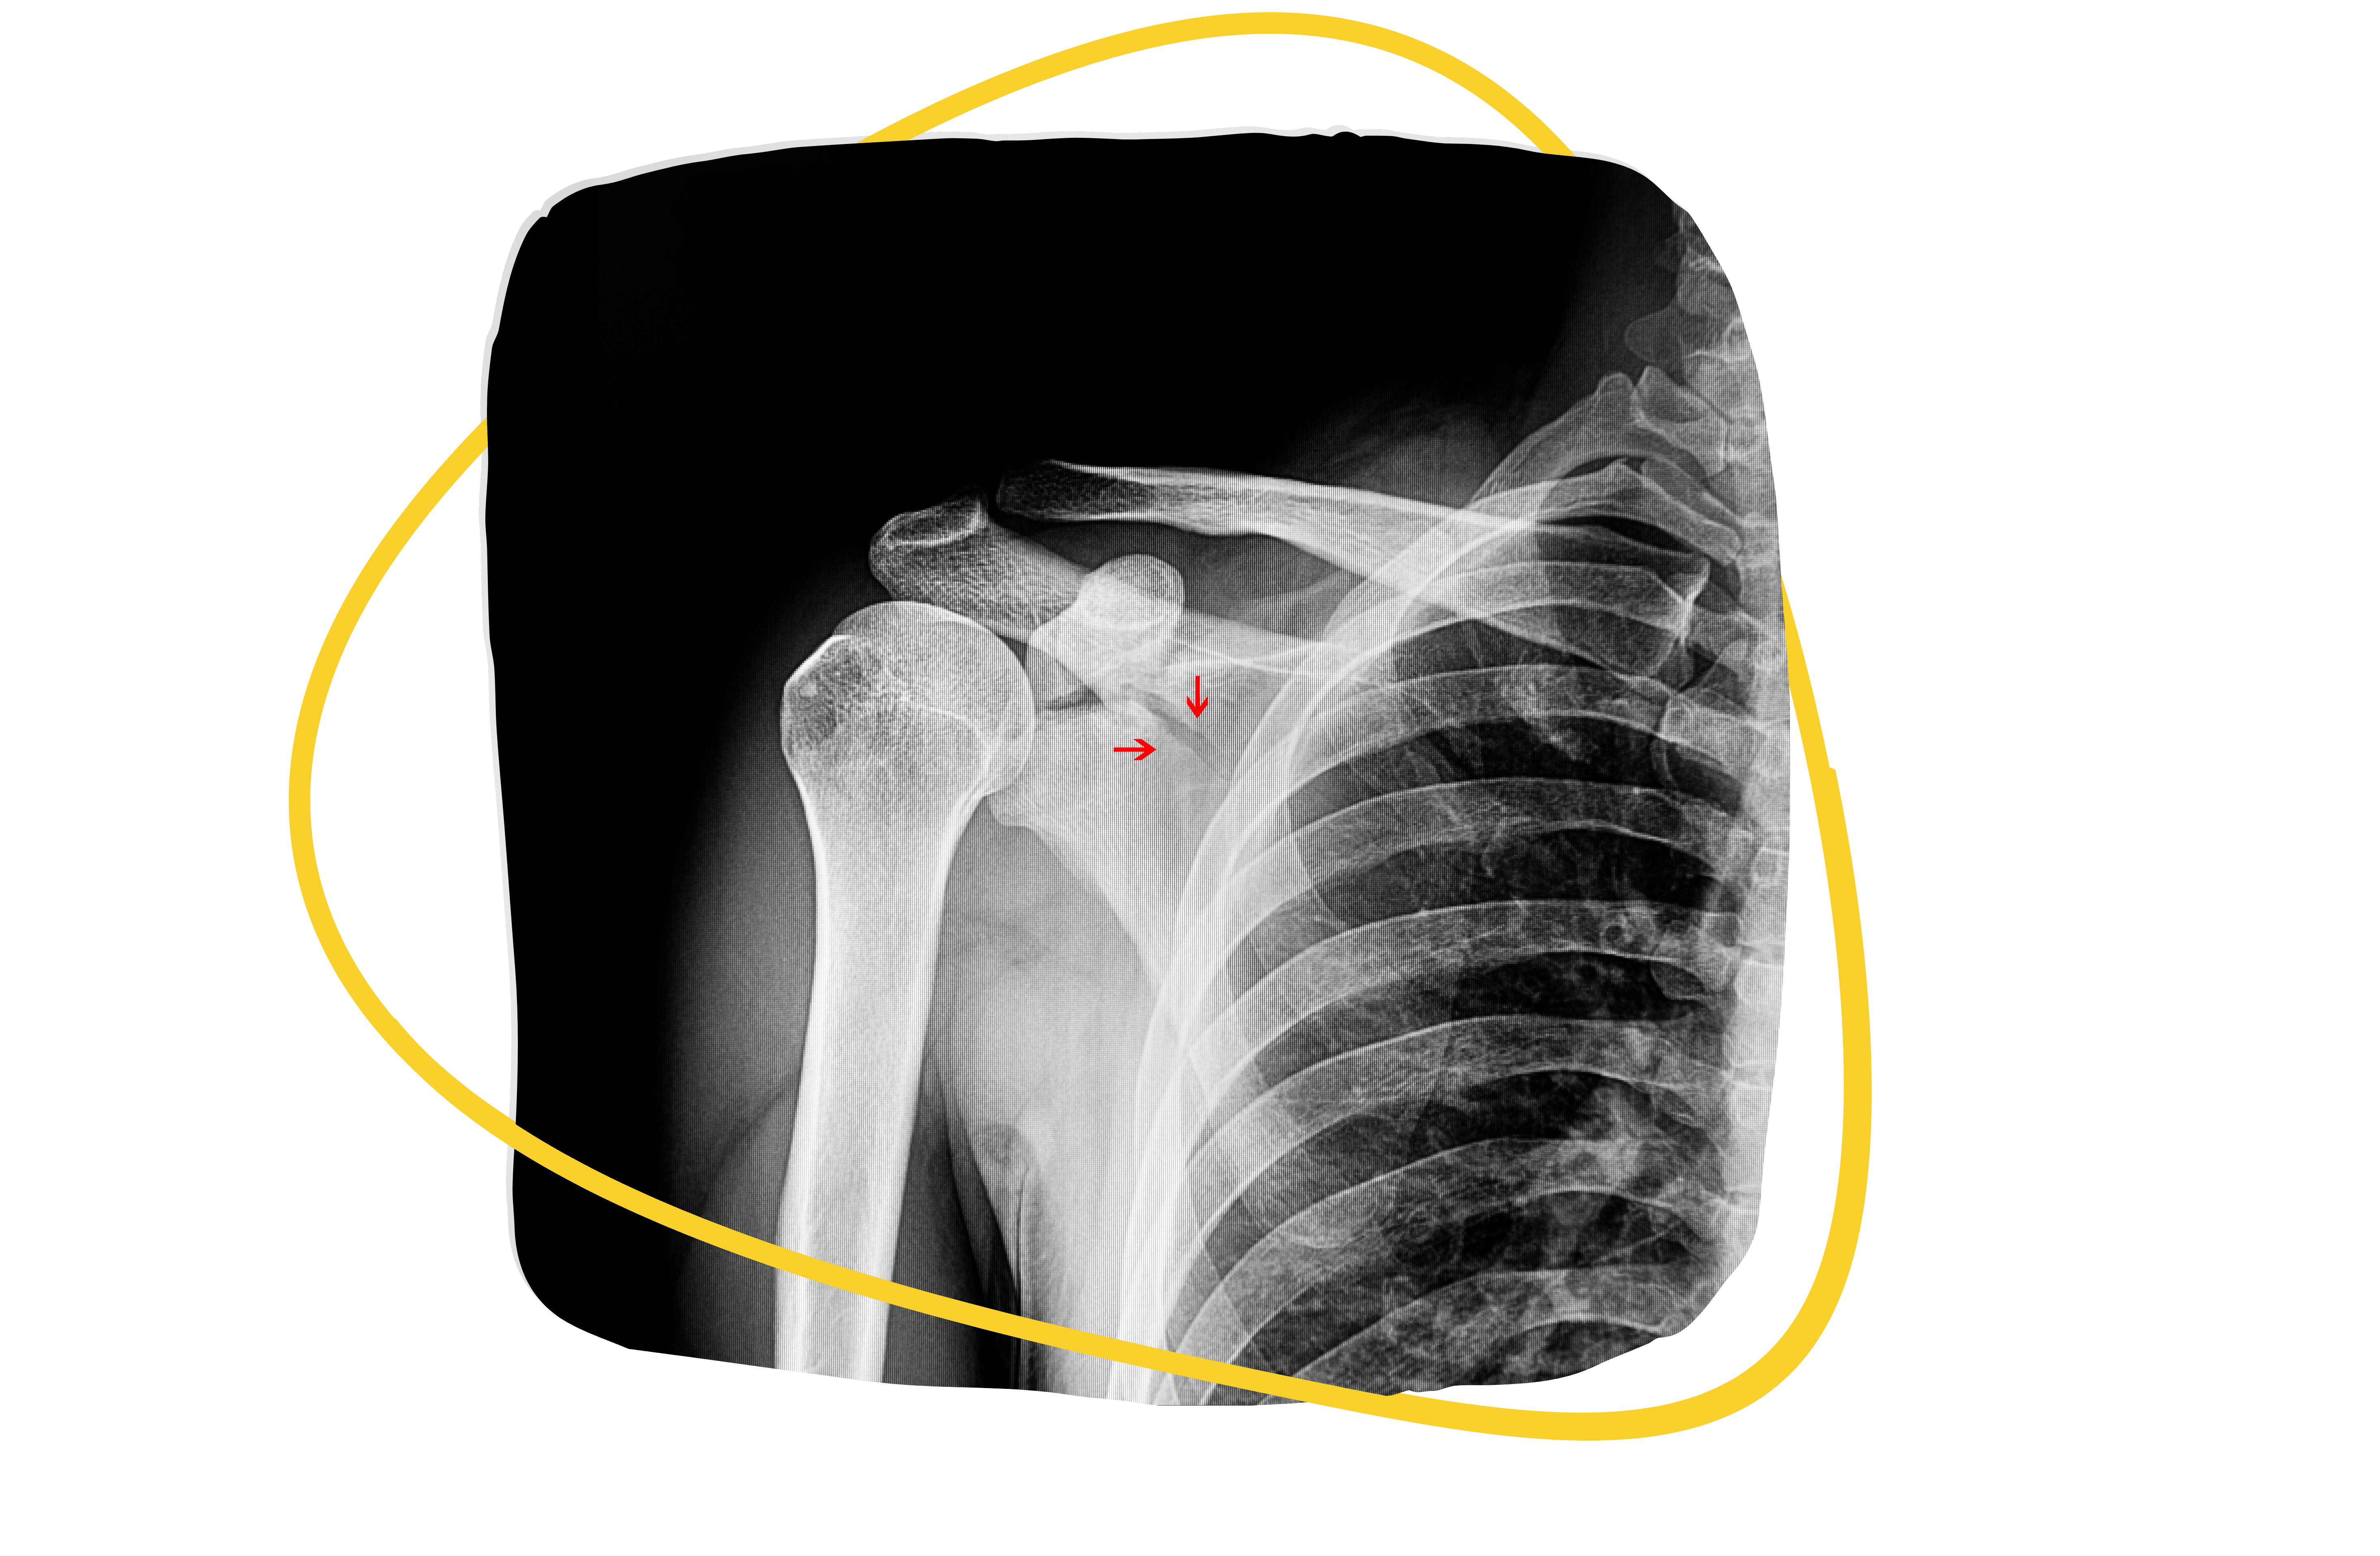

Musculoskeletal Imaging Certification

Optimize the management of every patient with our comprehensive certification for clinicians who order, recommend, or refer for musculoskeletal imaging. Learn when and why imaging is indicated, what studies are most appropriate, and how to communicate findings to patients and other healthcare providers.